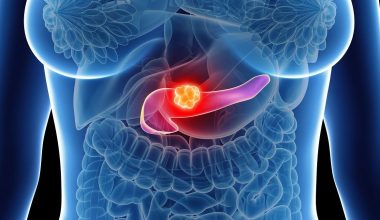

Ο καρκίνος του νεφρού, θα πρέπει να γίνει γνωστό πως συγκαταλέγεται στις 10 πιο κοινές μορφές καρκίνου παγκοσμίως, τόσο για άνδρες όσο και για γυναίκες.

Στοιχεία από το 2020 δείχνουν πως περίπου 180.000 άνθρωποι πέθαναν από τη νόσο μέσα στη χρονιά.

Παρά τον επιπολασμό του, μερικά από τα προειδοποιητικά σημάδια μπορεί να είναι δύσκολο να εντοπιστούν.